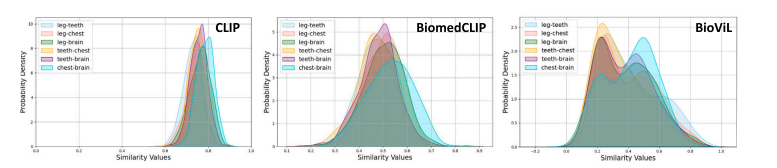

Fig. 17. Comparison between non-domain-specific and domain-specific pre-training. CLIP (OpenAI) tends to present high inter-disease similarity, which is significantly alleviatedin BiomedCLIP and BioViL, revealing the irrationality of adopting CLIP (OpenAI) in medical applications.

图17:非特定领域预训练和特定领域预训练之间的对比。CLIP(OpenAI公司的版本)往往表现出较高的疾病间相似度,而这种情况在BiomedCLIP和BioViL中得到了显著改善,这表明在医学应用中采用CLIP(OpenAI公司的版本)存在不合理性。